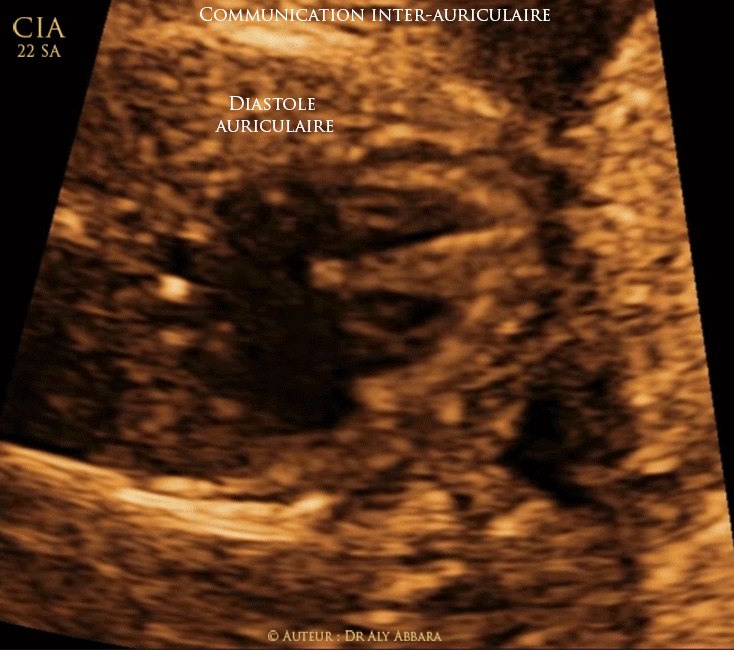

Vidéo et image animée échocardiographiques avec Doppler-couleur montrant une malformation cardiaque congénitale isolée ; il s'agit d'une communication inter-auriculaire (CIA) ou atrial septal defect (ASD).

Cette CIA se situe au centre du septum interauriculaire, au niveau du foramen ovale avec l'impossibilité d'identifier les éléments anatomiques de sa valve (Valvulus de Vieusens) qui doit normalement battre dans l'oreillette gauche.

Le Doppler couleur montre un flux sanguin bidirectionnel sur cette communication interauriculaire.

Le diagnostic retenu est de celui de communication interauriculaire type ostium secundum (CIA OS ou CIA II), ou un anévrysme du valvulus de Vieusens avec l'impossibilité échographique d'identifier les éléments anatomiques de cette valve.

Fœtus âgé de 22 SA.